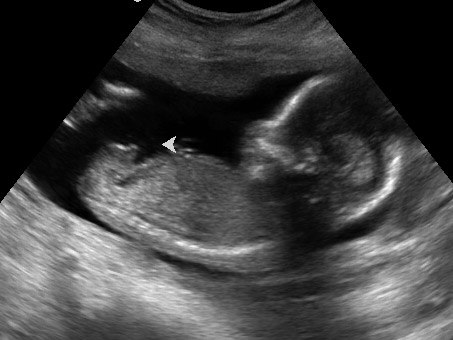

Jeg havde jo gået og undret mig over at jeg i 1. graviditet allerede mærkede liv i uge 16 og ikke rigtigt endnu denne gang. Så havde fået gjort mig selv ret nervøs da jeg havde en klar forventning om at jeg ville mærke liv før eller senest samme tidspunkt som sidst. Så var kommet ud i et skrækscenarie om at det måske var fordi der var noget galt, og at det var derfor babyen havde set lille ud til NF scanningen (blev rykket 8 dage tilbage). Da der er 1 mnd til MD scanning besluttede jeg mig for at bruge 500 kr på en privat scanning så jeg kunne blive beroligt med at der var liv i babyen og at alt så fint ud.

Vi var til scanningen i dag og der var godt liv i maven, så det var rigtig rart. Er meget lettet og tror på at jeg kan få slappet mere af frem til MD scanningen nu.

Alexander havde sagt at han mente det blev en baby med tissemand og det fik han ret i. Han skal have en lillebror

Vedhæftede fotos (klik for at se i fuld størrelse)